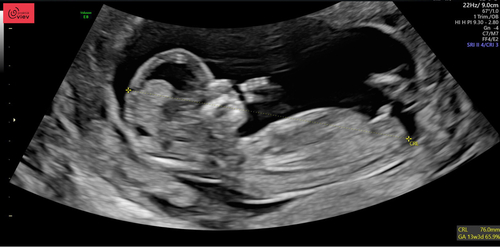

Ik ga het hier nog een keertje proberen, wat denken jullie? Hier 13+1 🫶🏻

Wat denken jullie 🩷 of 🩵? 13 weken en 2 dagen

12 weken.. Is het al te zien en zo ja wat denken jullie? Ben zoooo benieuwd!!🩵🩷

Nog net geen 12 weken, 11+6. Toch iets te nieuwsgierig of jullie al een gokje kunnen wagen.